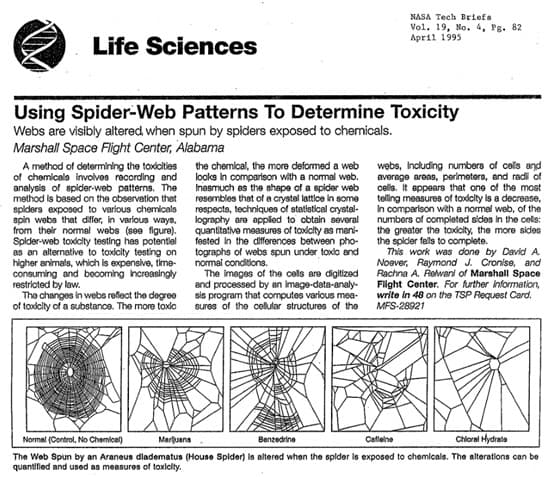

1948 年,瑞士藥理學家Peter N. Witt研究精神活性藥物對蜘蛛的影響,包括安非他命、麥斯卡林、LSD 和咖啡因,發現這些藥物會影響網的大小和形狀,變得不規則。1995 年NASA的一個研究小組復刻了Witt的實驗,質量上與 Witt 的結果相似,但新穎之處在於,蜘蛛網的模式被現代統計工具定量分析,並被提議作為一種靈敏的藥物檢測方法。